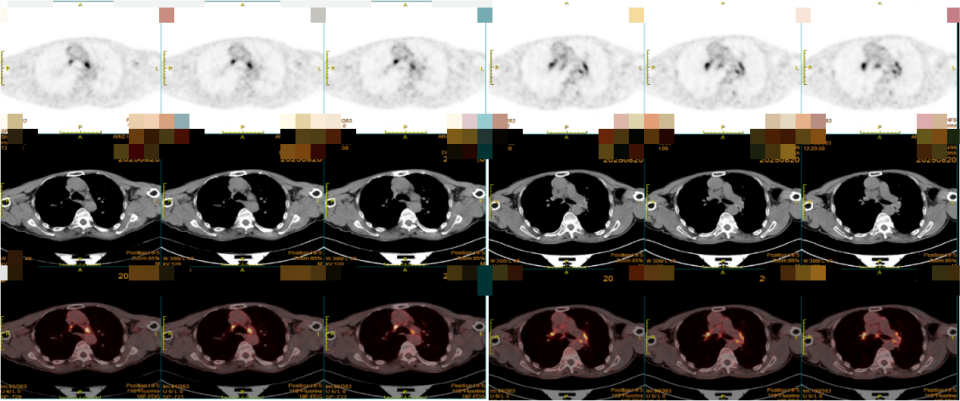

经过进一步病史询问和查体,并未找到白塞病的依据。根据上述科室建议,我们进一步完善PET/CT,检查结果回报:左锁骨区、纵隔、两肺门多发淋巴结糖代谢增高,考虑炎性增生可能;余纵隔、肺动脉区均未见高摄取(图5)。

图片

图5:PET/CT显示纵隔多发淋巴结高摄取

仅有纵隔淋巴结高摄取,似乎无法把自身免疫病、肺动脉狭窄/扩张、肺静脉闭塞这些病因联系在一起。结合此前考虑的病因,纤维素性纵隔炎、大动脉炎都没有在PET/CT中出现特定部位的高摄取表现;白塞病方面无法满足诊断条件。那还有什么疾病可能出现相应的变化?